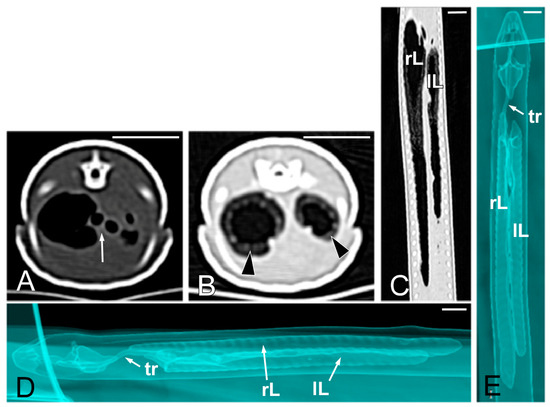

Concerning the CT images, the bifurcation of the trachea into the main bronchi was most clearly observed in the transverse plane (Figure 8A). The two lungs appeared as elongated structures with a reticular hypoattenuating area around an air-filled cavity. The distinction between the hypoattenuating area and just air was more distinctly identified in the transverse and dorsal planes using a postprocessing lung algorithm (Figure 8B,C). The 3D volume rendering using a postprocessing airways algorithm detailed the trachea and lungs (Figure 8D,E). Between the lungs, it was possible to identify those esophageal segments containing gas. On the contrary, those esophageal segments without intraluminal gas were indistinguishable from the surrounding soft tissues. The transverse and dorsal planes were the most useful for recognizing the esophagus (Figure 9). The liver appeared as an elongated organ with soft tissue attenuation located ventral to the caudal midsection of the lungs, on the right side of the stomach. Its margins were not well defined. The gall bladder was identified in the ventral part of the coelomic cavity as a hypoattenuating small oval structure surrounded by the hepatic parenchyma (Figure 10A). The differentiation between the gall bladder and the hepatic parenchyma was more evident in the postcontrast studies (Figure 10B–D). As in the case of the esophagus, the stomach and the small and large intestines were easily distinguished when containing intraluminal gas (Figure 11A) or hyperattenuating content (residual ingesta) (Figure 11B). The small and large intestines were located just caudal to the liver and the stomach, occupying approximately the caudal third of the coelomic cavity. The spleen and pancreas could not be identified when using CT.

Figure 8.

The CT images of Pseudopus apodus in the transverse (A,B) and dorsal (C) planes, and the 3D volume rendering showing the airways (D,E). Image (A) was obtained with a soft tissue algorithm and shows the main bronchi bifurcation (white arrow), while images (B,C) were postprocessed using a lung algorithm and show the peripheric hypoattenuating area (black arrowheads) around an air-filled cavity. The images (D,E) were postprocessed using the 3D volume rendering with airways algorithm and offer a detailed representation of the trachea (tr) and lungs (L). Bar = 10 mm.

The slow respiratory rate, together with enhanced contrast between lung parenchyma and air, has been reported as a factor to obtaining exceptional CT images of chelonian and snake respiratory tracts [29,30,31,44]. In our work, the trachea, the main bronchi bifurcation, and the lungs could be perfectly differentiated in 2D and 3D volume rendering images. The sagittal plane was the most adequate for evaluating the entire trachea, the transverse plane for identification of the main bronchi bifurcation, and the transverse and dorsal planes to examine the lungs in 2D images. Ricciardi et al. [38] suggest that CT may be a potentially suitable technique for diagnosing a great variety of pulmonary pathologies in reptiles, whereas Gumpenberger [46] considers CT as the gold standard for images of the respiratory tract in all reptiles. This is because it allows for precise visualization of the upper respiratory tract, but especially of the variable delicate architecture of the lungs in the different species, especially with lung or bone algorithms. In our work, only the lung algorithm allowed us to differentiate the peripheric reticular hypoattenuating area from the air-filled central cavity in the lungs. The trachea and main bronchi bifurcation were easily identified in our study due to the air content.